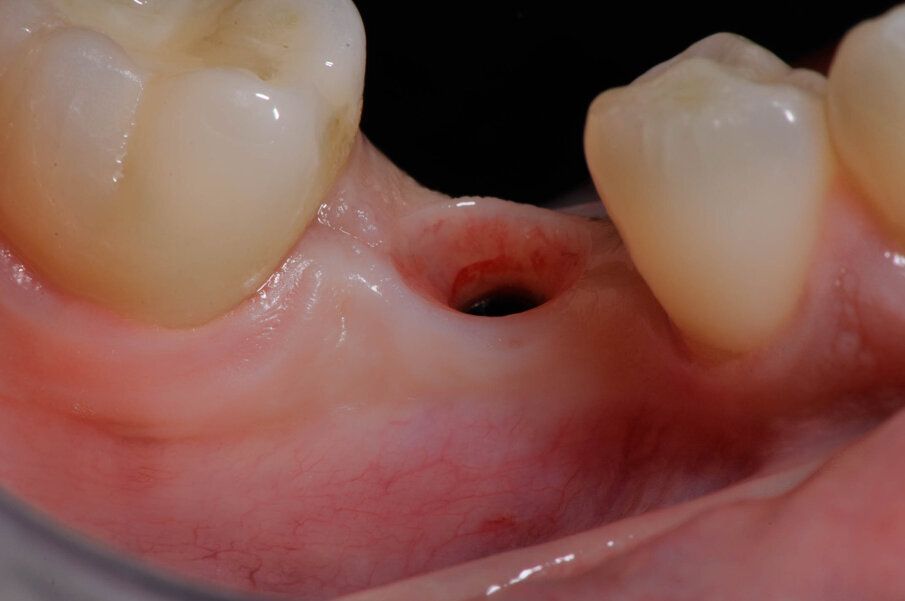

Fig. 14_La qualità dei tessuti del tragitto transmucoso grazie alla rilocazione del margine del pilastro implantare Dentsply Sirona Ankylos.

Fig. 17_Dettaglio tragitto transmucoso.